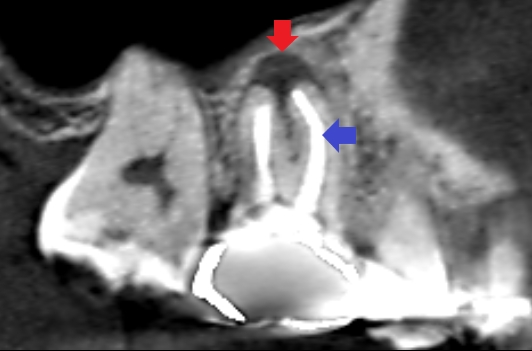

初診時のCT画像です。

赤い矢印の先に膿の影がみられます。青い矢印の先の近心頬側根の根管充填は、根の先にまで到達し上手く根管治療できているようにみえます。

しかし、CTの画像を少しずらしてみると、同じ近心頬側根の中にもう一つの未治療の根管がみられました。青い矢印の先に黒い筋がみられます。これが未治療の根管です。